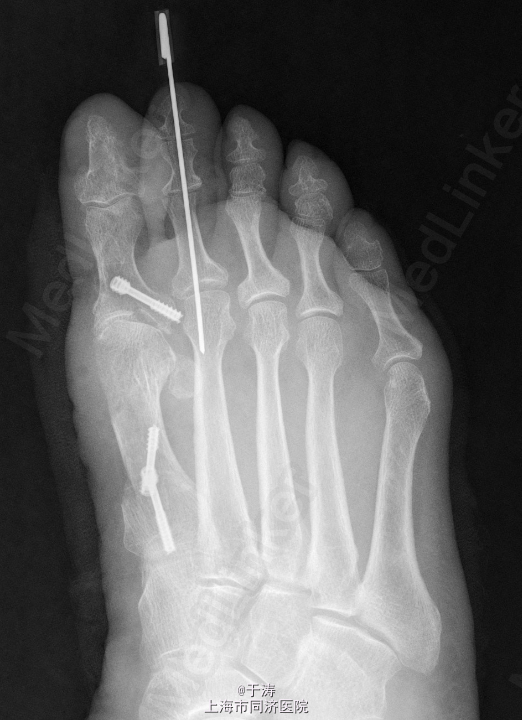

诊断:右足拇外翻,跖痛症,第2趾锤状趾 处理:拇外翻截骨矫形+软组织松解+Akin手术+第2趾近侧趾间关节成形

随访:术后6周,外形可,内固定在位。 讨论:拇外翻是足踝外科最常见畸形之一,生物力学机制复杂,手术方式众多,每个患者畸形不尽相同,需根据每个患者因地制宜。